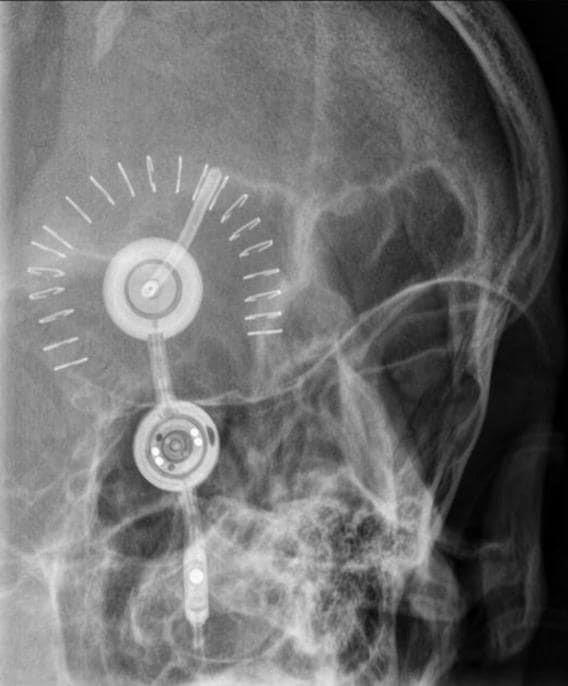

종류는 codman이고, 대조표와 동일하게 proximal 부분이 위쪽, indicator가 우측에 위치해 있다. 그대로 읽으면 되므로, 6cmH2O(60mmH2O)가 된다.